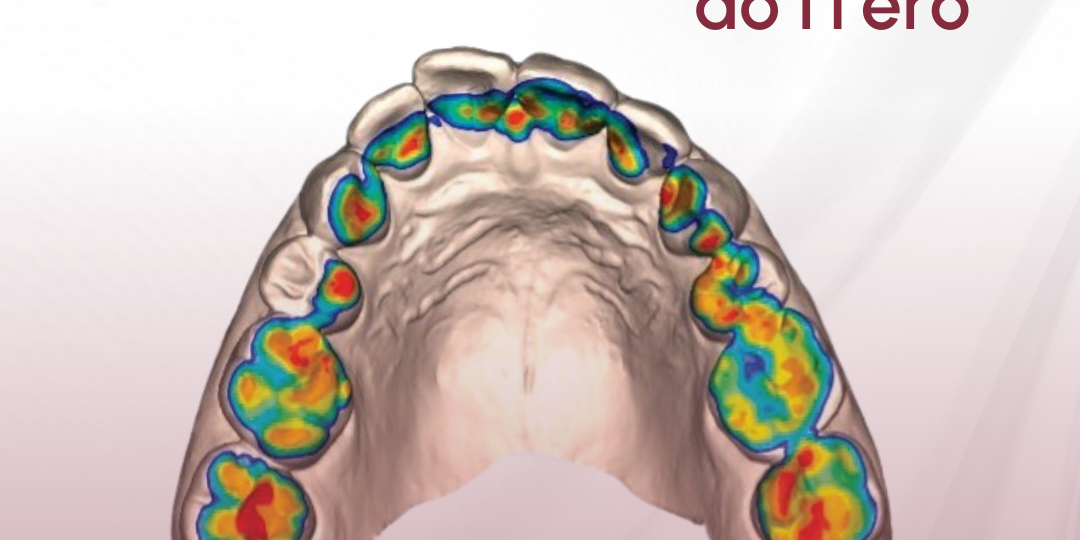

Com o Oclusograma do iTero, os pontos de contato oclusal dos seus pacientes não passam despercebidos! Essa tecnologia avançada permite identificar sobrecargas oclusais com precisão e rapidez, garantindo mais segurança e previsibilidade no planejamento odontológico.

– Avalie os contatos oclusais em segundos, direto no scanner;

– Planeje reabilitações, ajustes e tratamentos ortodônticos com confiança;